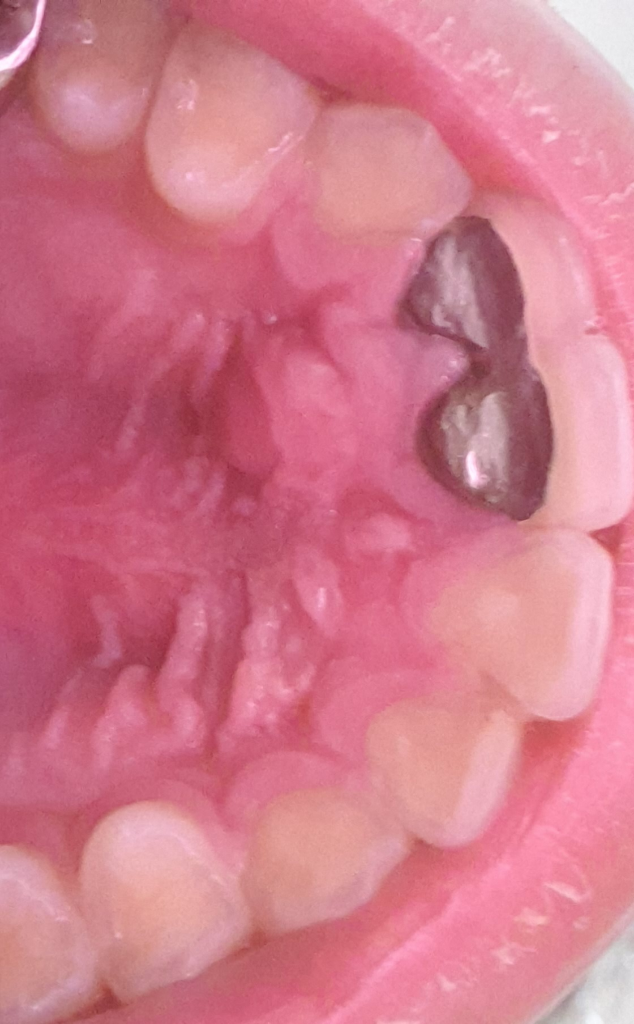

입천장이 부었습니다 부은 이유가 무엇일까요?

제가 어제 아주 뜨거운 오리고기를 먹어서 입천장을 데였었는데 그 후1시간2시간정도있다가 앞니 쪽 입천장에 물혹같은게 점점 생겼습니다

그런데 생긴 위치가 약5년전에 치과치료를 한 이빨

바로뒤편이라 정말 데여서 부은건지 아니면 염증인지 궁금합니다

이빨에 큰 통증은없고 부은부분 입천장에 압박감이 좀 있습니다 물을 어금으면 물혹느낌이 나구요

첫번째사진이 어제고 두번째사진이 오늘인데 크기가 커지진않은것 같습니다

• 1번 째 사진

• 2번 째 사진

잇몸에 데여서 물이 찬 것으로 보입니다. 시간이 지나면 없어질 수도 있으나 안없어지면 치과에서 째야합니다.

사진으로만 봤을 경우에는 찍은 단 부위에 염증이 생겼을 가능성이 있습니다 자세한 확인을 위해서는 해당 부위에 방사선 사진이 필요할 것으로 생각됩니다 치과 병원에서 자세한 검사를 받아 보는 것을 권해 드립니다

엑스레이 사진을 찍어보셔야될것같습니다. 아마도 치아 뿌리끝에 염증이 생긴게 아닐까 생각됩니다.